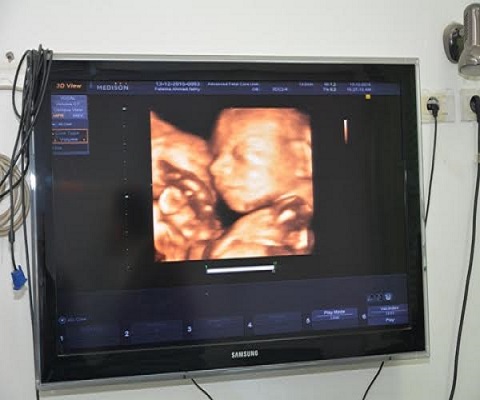

كما يساهم الفحص فى تحديد مسببات نزيف الحمل ومشاكل نمو الجنين وذلك عن طريق إجراء صورة مجسمة رباعية الأبعاد وأشعة متقدمة عن العيوب الخلقية للأجنة وأشعة تشريحية باستخدام أجهزة الوحدة من أجهزة فحص ثلاثي الأبعاد ونبض الجنين وأجهزة دوبلار .